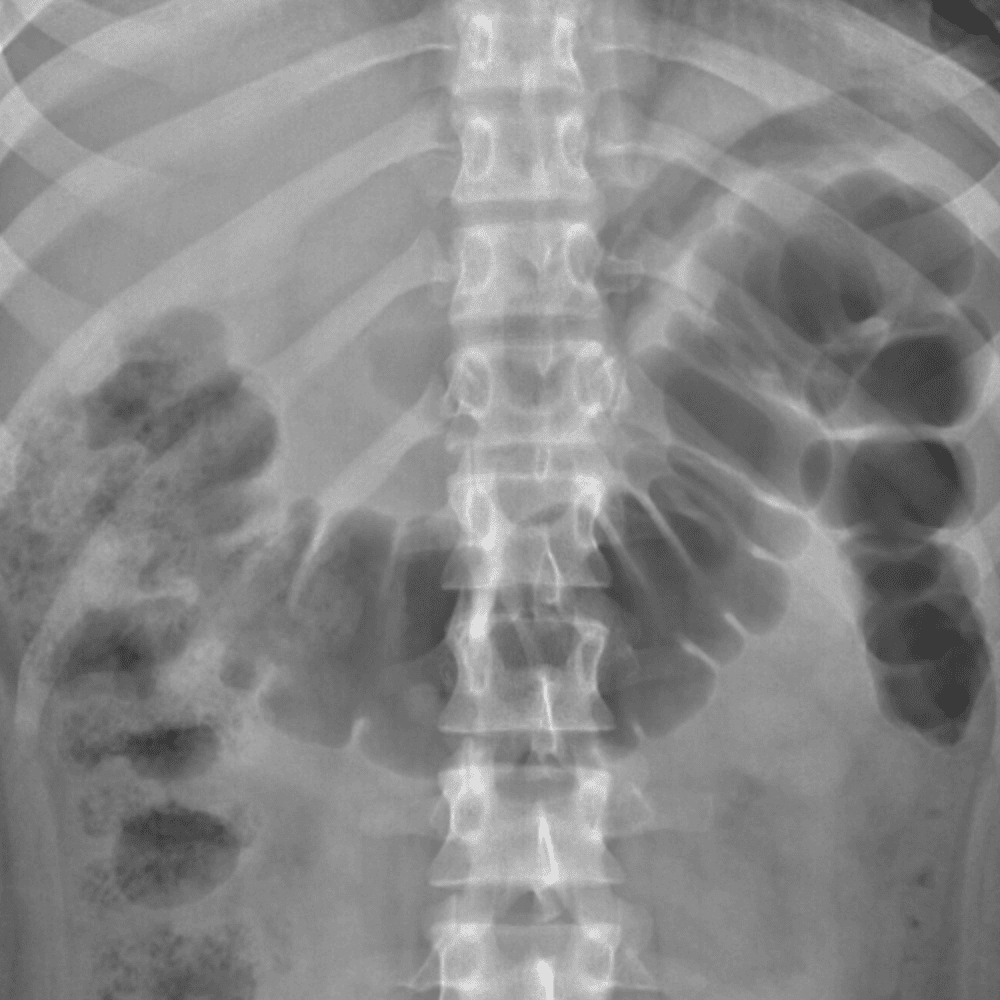

Peds Abdomen

Practice

Simulates call by including subtle or difficult cases and some normals.

30 cases